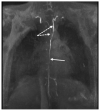

Background: Clinical examination and lymphoscintigraphy are the current standard for investigating lymphatic function. Magnetic resonance imaging (MRI) facilitates three-dimensional (3D), nonionizing imaging of the lymphatic vasculature, including functional assessments of lymphatic flow, and may improve diagnosis and treatment planning in disease states such as lymphedema.

Results: From 612 identified articles, 43 articles were included and their protocols and results summarized. Field strength was 1.5 or 3.0 T in all studies, with 25/43 (58%) employing 3.0 T imaging. Most commonly, imaging of the peripheries, upper and lower limbs including the pelvis (32/43, 74%), and the trunk (10/43, 23%) is performed, including two studies covering both regions. Imaging protocols were heterogenous; however, T2 -weighted and contrast-enhanced T1 -weighted images are routinely acquired and demonstrate the lymphatic vasculature. Edema, vessel, quantity and morphology, and contrast uptake characteristics are commonly reported indicators of lymphatic dysfunction.